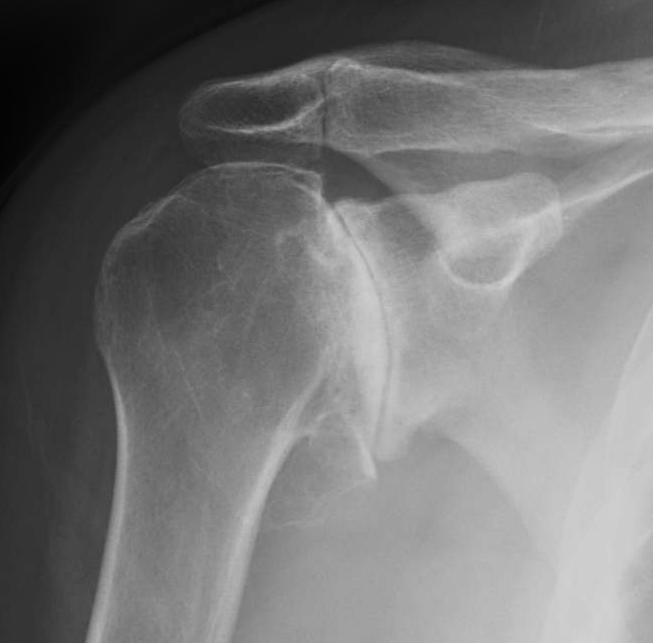

shoulder xray oa 4

Late osteoarthritis shoulder